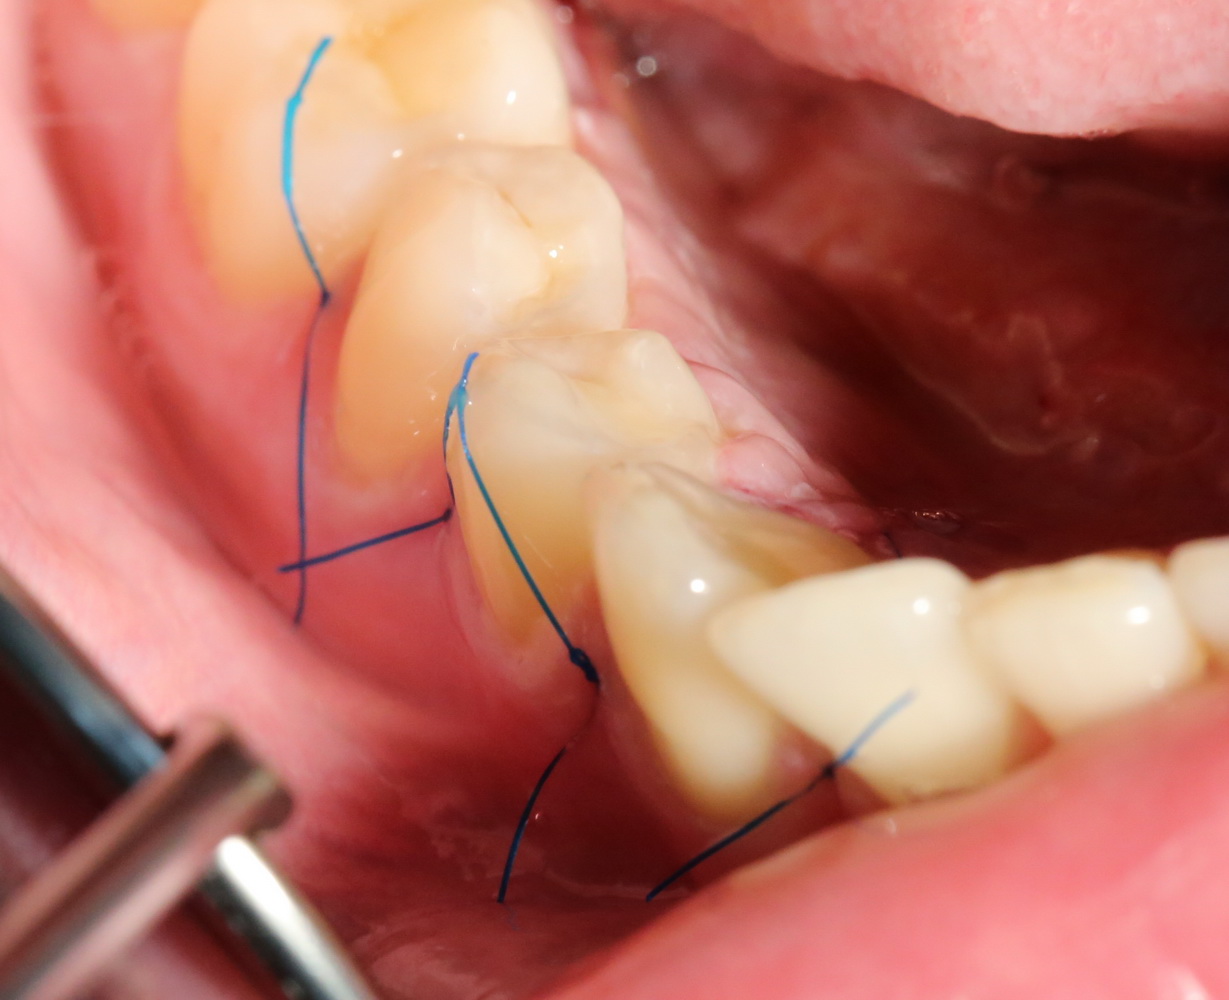

Благодаря сделанному нами разрезу, мы можем вывести узелки на внешнюю сторону альвеолярного отростка, что будет удобнее и комфортнее для пациента:

Операция закончена.

Вот фотография послеоперационной раны через пару дней:

Так, друзья, выглядит нормальная послеоперационная рана. Со швами я угадал. Это, кстати, Prolene 5-0.